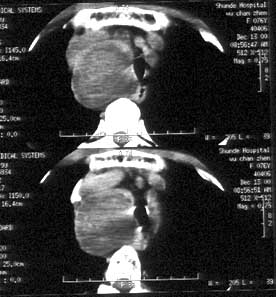

图:甲状腺结节伴点状钙化

实际上,点状钙化即微钙化表现为点状强回声,不论后方是否出现声影,可见于40%~61%的乳头状癌,但也可见于其他良性和恶性病变,如滤泡状癌、分化不良性癌、结节性甲状腺肿、滤泡状腺瘤和桥本氏甲状腺炎等。粗钙化多见于良性结节,尤其是结节性甲状腺肿。边缘钙化指位于甲状腺结节边缘部位的钙化,常见于结节性甲状腺肿,是良性结节的标志。